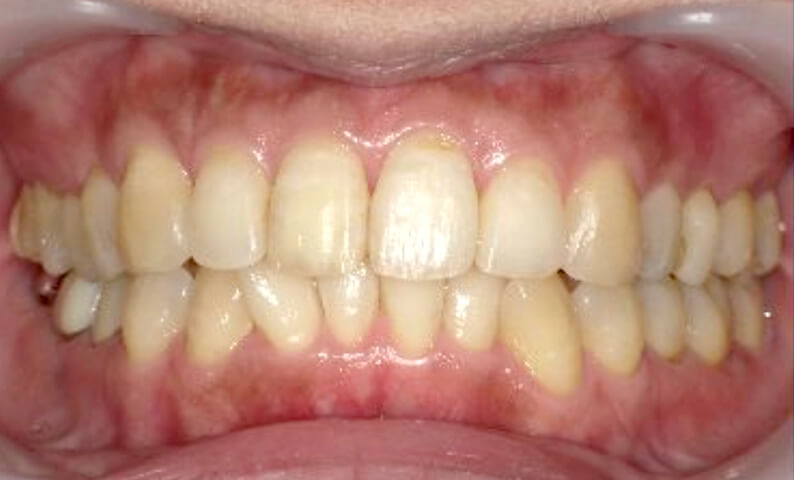

症例_003 上下顎の部分矯正

治療期間:12ヶ月金額:54万円+税男性八重歯前歯のガタガタ

| Before | After |

|---|---|

|